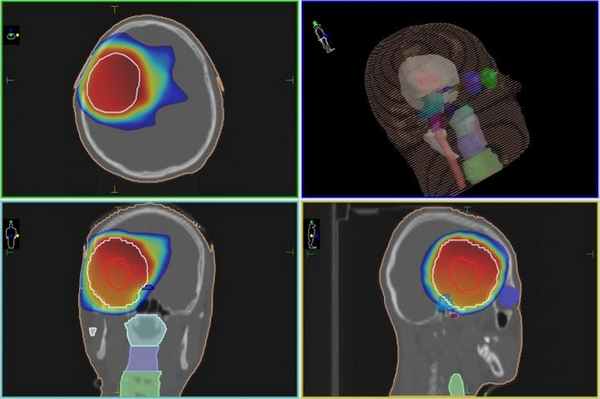

Радиохиругическое лечение глиомы на Киберноже, независимо от типа опухоли, который более точно можно будет определить во время биопсии (если есть возможность ее провести), проводится по одинаковому алгоритму. Сначала с помощью данных КТ- и МРТ-исследований будет сформирована пространственная модель расположения опухоли и соседствующих с ней здоровый участков мозга. Затем в планировочной системе лучевой терапевт задает требуемую дозу, которую КиберНож должен сформировать в области, в границах которой находится глиома.

Также задается минимальная доза в тех зонах, которым любое облучение противопоказано (например, ствол головного мозга). После этого мощная компьютерная система строит план лечения с тем, чтобы из множества тонких одиночных пучков излучения сформировать в опухолевой зоне равномерную зону требуемой дозы излучения. Далее роботизированная рука-манипулятор КиберНожа согласно составленному плану будет последовательно перемещать компактный линейный ускоритель в каждое из запланированных положений, из которых будет проводится подача единичного пучка.

План радиохирургического лечения глиомы на КиберНоже

План лучевого лечения глиомы на линейном ускорителе